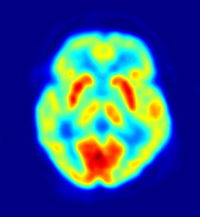

تصوير مقطعي بابتعاث البوزيترونات

التصوير المقطعي بالإصدار البوزيتروني إنگليزية: Positron Emission Tomography أو PET تقنية تصوير في الطب النووي تسفر عن معطيات وصور ثلاثية الأبعاد لمجرى مختلف العمليات الوظيفية في الجسم. ويعمل الجهاز المصوّر على أساس اكتشاف أزواج من أشعة غاما المنبثفة بشكل غير مباشر عن نظير مشع مصدر للبوزيترونات (قائفة مشعة)، والتي يتم إدخالها إلى الجسم بعد أن ترتبط بجزيء فعال حيويًا). من ثم، يتم استبناء الصورة ثلاثية الأبعاد من الإسقاطات بشكل محوسب. في الآونة الأخيرة، أصبحت تستعمل أجهزة تسهل الاستبناء بواسطة استعمال التصوير الطبقي المحوسب بواسطة الأشعة السينية (أشعة إكس) والذي يتم إجراءه في نفس جهاز التصوير بالإصدار البوزيتروني وفي نفس الوقت.

وفق الإحصائيات الملتقطة من تزامن اصطدام أزواج فوتونات بالمفراس، بالإمكان حل هيئة معادلات لكمية فعالية القائفة المشعة في كل قطعة من النسيج المنشود على طول عدّة خطوط LOR. بهذا الشكل يتم تخطيط النشاط الإشعاعي لكل فوكسل في النسيج. الصورة النهائية تظهر جميع الأنسجة التي تركزت فيها القائفة المشعة، وهي صورة يستطيع أخصائي أشعة أن يقرأها ويستخلص منها الاستنتاجات.